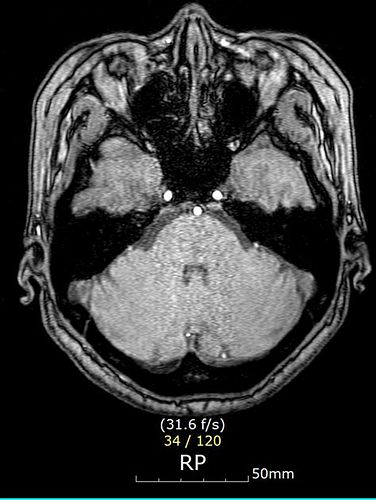

뇌 MRI (자기공명영상) 검사

- 비급여(보험 미적용) 시 평균 비용

- 25만 원(최저) ~ 88만 5천 원(최고), 평균 약 45만 8천 원.

- 종합병원: 40~50만 원, 상급종합병원: 80~90만 원에 이르는 곳도 있음.

- 일부 병원에서는 40만 원 선으로 안내하는 경우도 있음.

- 건강보험 적용 시

- 의사의 의학적 판단 하에 뇌출혈, 뇌경색 등 뇌질환이 의심될 때만 적용.

- 보험 적용 시 대학병원은 약 18만 원, 일반병원은 약 9~18만 원 수준까지 낮아짐.

- 보험 적용 여부는 반드시 의료진의 진단 및 기준에 따라 결정됨.

- 단순 두통·어지럼 등 증상만으로는 적용이 제한될 수 있음.

MRI 검사 비용

- 비급여(보험 미적용) 기준

- 일반적으로 35만~70만 원 선에서 많이 책정됨.

- 대학병원, 대형병원: 50만~70만 원, 일부는 100만 원까지도 가능.

- 지역 중소병원, 의원: 35만~50만 원 수준.

- 실제 예시: 포항시 에스포항병원 뇌 MRI 60만~70만 원, 사랑의병원 48만~40만 원(검진시 할인가).

- 본인 부담금 약 15만~30만 원(검사 목적 및 병원에 따라 다름).